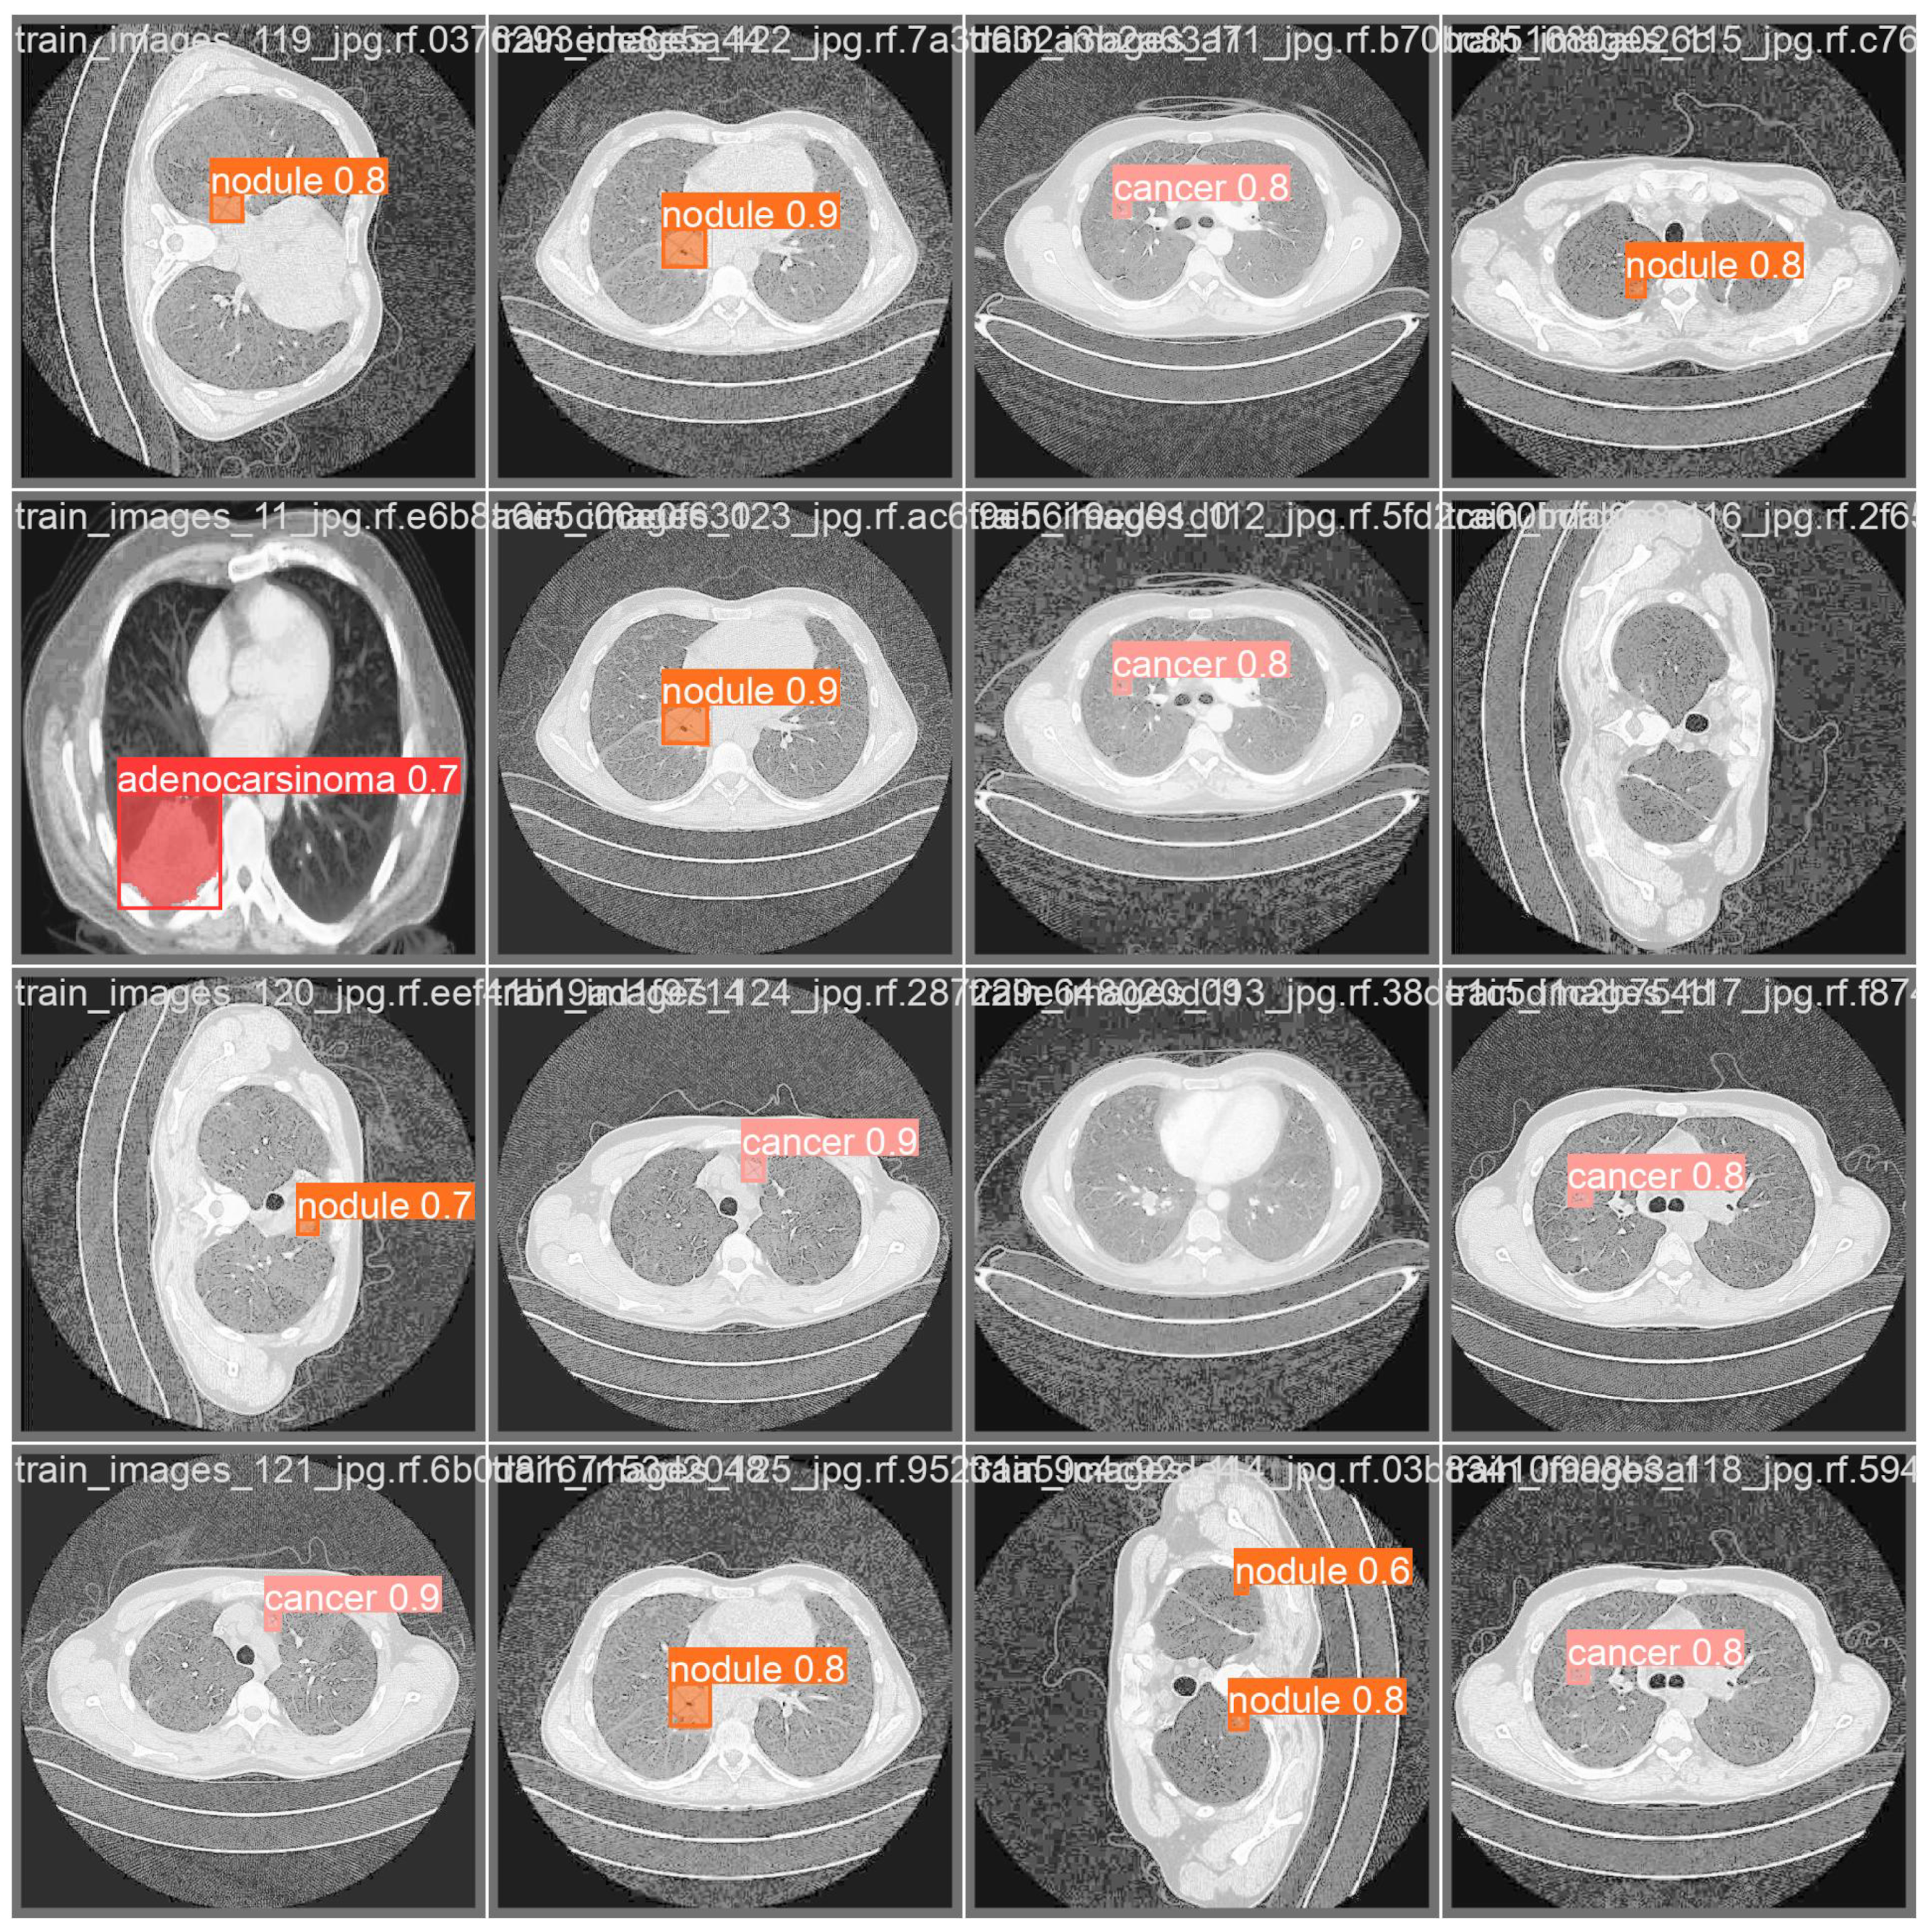

- Adenocarcinoma (Blue Line):

- -

- The blue line represents the precision–recall relationship for the adenocarcinoma class.

- With an average precision (AP) of 0.734, the model performs relatively well in detecting adenocarcinoma, maintaining high precision and recall values.

- Cancer (Orange Line):

- The orange line represents the performance for the cancer class.

- An AP of 0.588 indicates moderate performance, with a noticeable drop in precision as recall increases, suggesting that the model struggles more with this class compared to adenocarcinoma and nodules.

- Nodule (Green Line):

- The green line shows the precision–recall for nodules.

- With the highest AP of 0.802, the model performs best on this class, indicating high precision and recall across most thresholds.

- All Classes (Bold Blue Line):

- The bold blue line represents the overall performance across all classes, with an mAP@0.5 of 0.708.

- The mean average precision (mAP) at an IoU threshold of 0.5 provides a single metric summarizing the model’s performance across all classes.

- An mAP@0.5 of 0.708 suggests that the model has a strong overall detection capability, balancing precision and recall well.